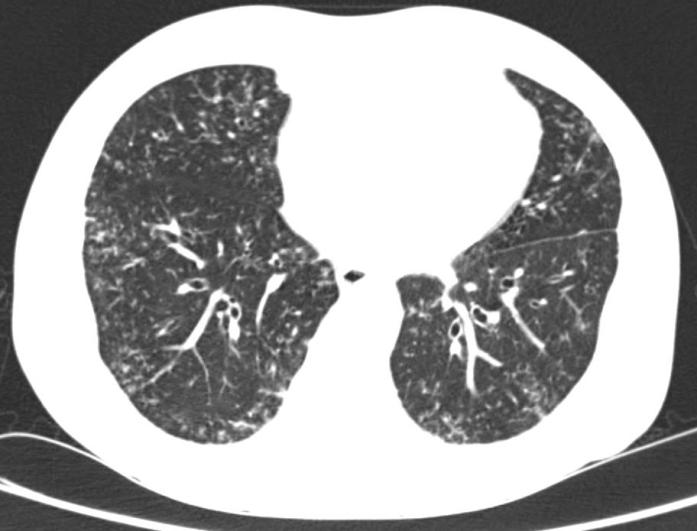

第8节:铜绿假单胞菌肺炎如何诊断

铜绿假单胞菌:弥漫性支气管肺炎 小叶中心结节 早期肺脓肿 胸腔积液